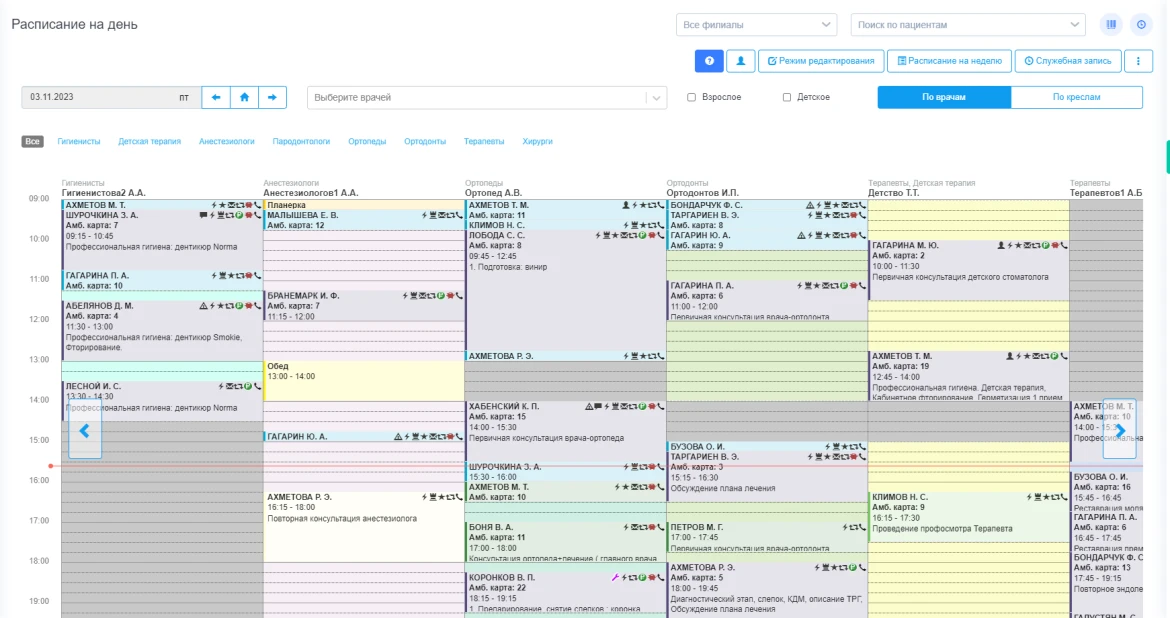

- Запись на прием: Удобная система онлайн-записи, позволяющая пациентам самостоятельно выбирать время и врача, а также получать напоминания о визитах.

- Управление расписанием: Эффективное планирование работы стоматологов, что помогает избежать накладок и улучшить доступность услуг.

| Автоматизация регистратуры | да |

| Управление филиалами | да |

| Лист ожидания | да |